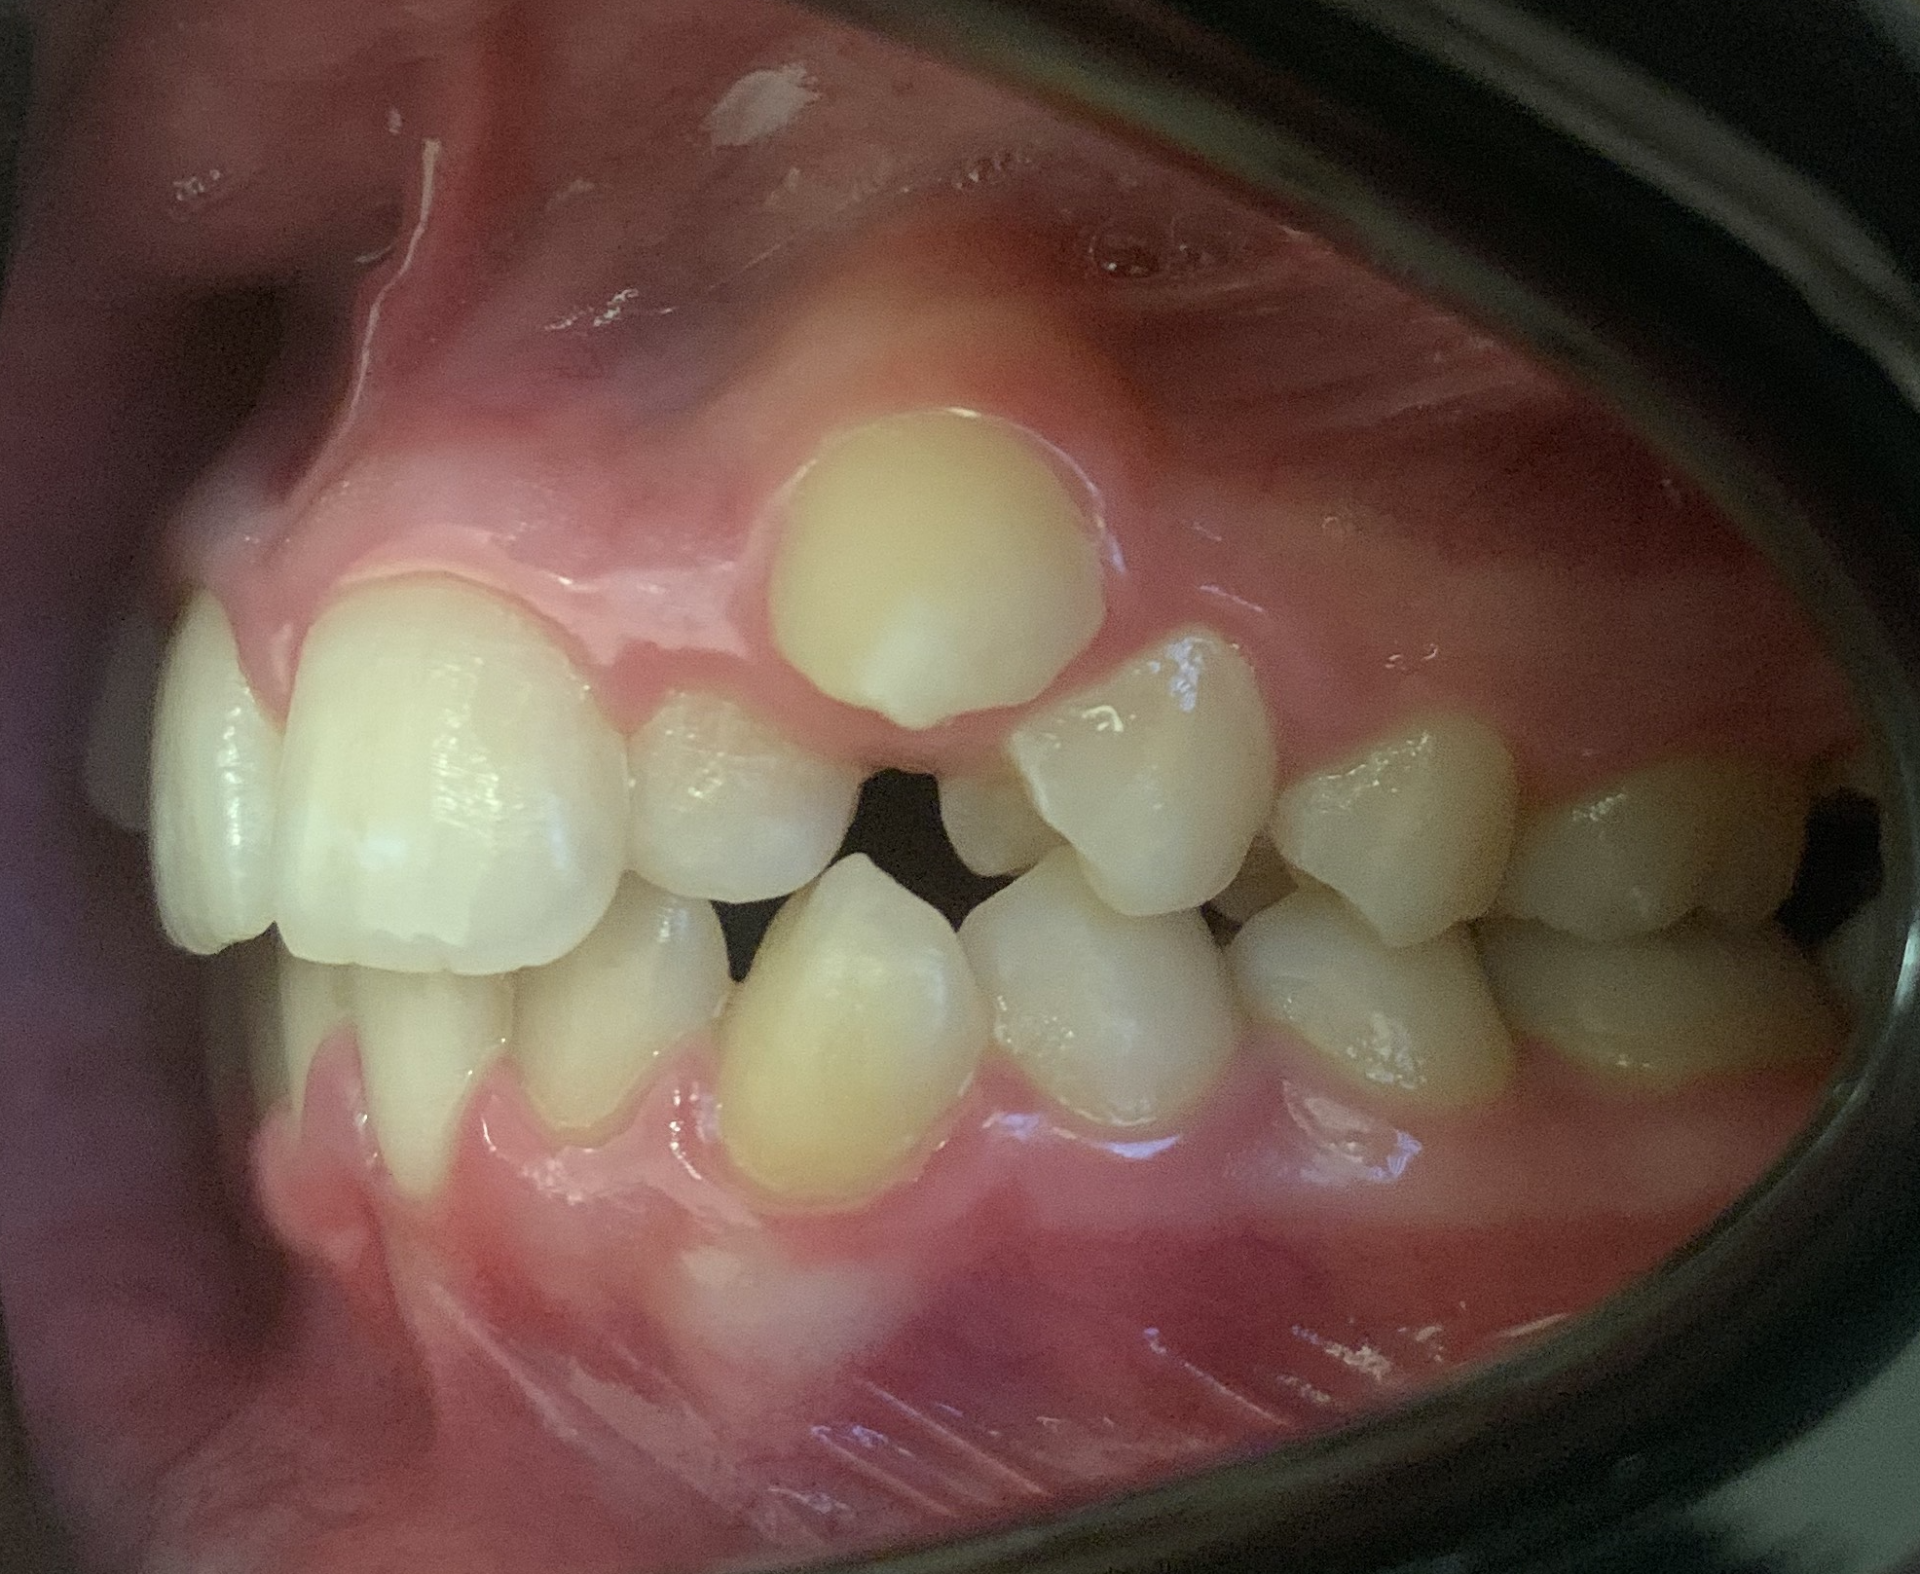

Anomalie d'éruption

Des dents définitives poussent à l’extérieur ou à l’intérieur des dents de lait qui gênent leur éruption